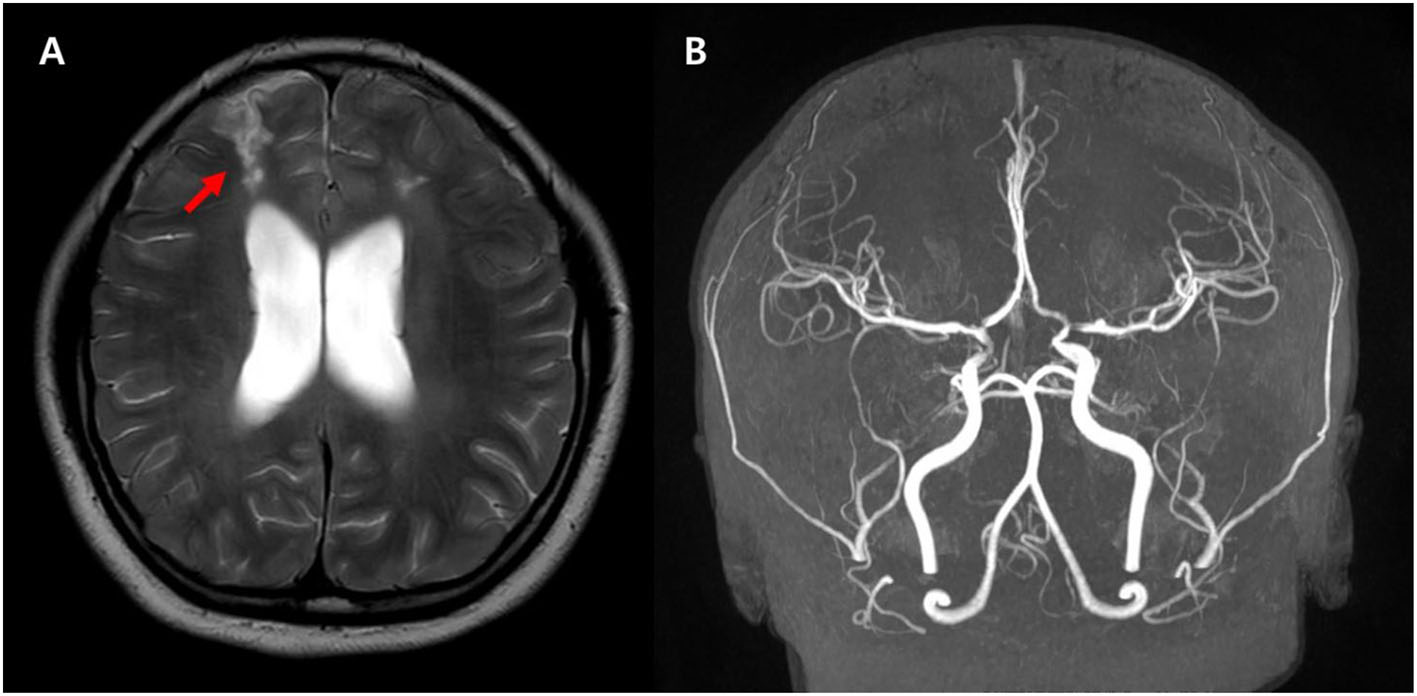

She was transferred to Samsung Medical Center with continuous alteration of mental status after the second seizure on the 12th day of hospitalization. On admission to this hospital, she was drowsy and sometimes confused. The patient consistently complained of severe headache. On the second hospitalization day, sudden weakness affecting both legs and dysarthria appeared. The symptoms waxed and waned during the day. On the third hospitalization day, her symptoms progressed into paraplegia and aphasia. Upon neurological examination, the Babinski sign and ankle clonus were positive bilaterally. The brain MRI on the day of transfer showed acute hemorrhage around the distal internal carotid artery (ICA) and right middle cerebral artery (MCA) obliterating the basal cistern and narrowing of both distal ICA and aneurysm at the left distal ICA (Figure 1). The brain MRI and magnetic resonance angiography (MRA) on the third hospital day demonstrated diffuse narrowing of bilateral MCAs, anterior cerebral arteries (ACAs), and distal ICAs, as well as small aneurysms at both distal ICAs (Figure 2D). In addition to the persistent SAH in the basal cistern and prepontine cistern, multifocal parasagittal acute infarctions were found (Figures 2A–C). Those findings raised the possibility of diffuse vasospasm associated with the SAH resulted from aneurysm rupture. The vessel wall MRI showed no contrast enhancement in the arterial wall, which could exclude the cerebral angiitis. Transfemoral cerebral angiography (TFCA) was performed on the sixth hospitalization day, revealing three unruptured aneurysms in both anterior choroidal arteries and left MCA and posthemorrhagic vasospasm involving both distal ICAs, MCAs, and ACAs (Figures 3A,F). The degree of narrowing of these cerebral blood vessels was severe for considering the endovascular coil embolization of the aneurysms. Therefore, we administered nimodipine and provided sufficient intravenous hydration to expand the vessels. On the seventh hospitalization day, after confirming that the vessels were widened enough to perform the intervention, we executed the first endovascular coil embolization for obliteration of unruptured aneurysms on the right anterior choroidal artery (Figures 3B–E). The upper motor neuron sign disappeared after the procedure. On the ninth hospitalization day, she became alert; however, the motor aphasia continued. She began to speak in sentences on the 15th day of hospitalization. On the seventeenth hospitalization day, we performed the second endovascular coil embolization for obliterating the left anterior choroidal artery aneurysm (Figures 3G–J). Although her brain MRI showed a slight reduction of infarction size compared to the previous results after the embolization, her clinical symptoms improved with the rehabilitation treatment. She was discharged on the forty-third hospitalization day without any motor deficit. The brain MRI and MRA performed 10 months after discharge demonstrated encephalomalacia in both parasagittal areas especially in the left frontal lobe (Figure 4). The electroencephalogram performed at that time showed epileptiform discharges in the left or right frontal areas. On her last follow-up in the outpatient clinic 14 months after discharge, her motor function was normal, and no neurologic deficit was observed.

Figure 2. Diffusion weighted image obtained at the time of onset (A,B) shows high signal intensity lesions at both parasagittal areas (arrowheads), and apparent diffusion coefficient (ADC) map (C) shows low signal intensity (arrows) suggesting acute cytotoxic edema. The brain magnetic resonance angiography (MRA) demonstrates diffuse narrowing of the cerebral arteries and small aneurysms (red arrows) at both distal internal carotid arteries (D).